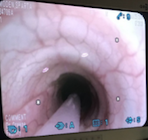

How does it work? This procedure, involves pushing a bronchoscope, or a probe with a camera on the end, through the airway. The probe progresses from the mouth, past the larynx, into the trachea, and then into one of the bronchi. These structures are visualized as the camera progresses to the bronchi, so we can see if any abnormalities are present. When the bronchus is reached, a small amount of fluid is discharged into the lungs and immediately suctioned back up. Samples were submitted to ISU for bacterial culture and for evaluation of the cells present in the lavage fluid (cytology).

Pictures from Sparta’s BAL. The left picture shows the probe passing through the larynx. The middle picture shows the probe in the trachea, and the right picture shows the probe at the bifurcation of the two bronchi. The probe was passed into one of the dark holes (bronchus) to lavage the lung.